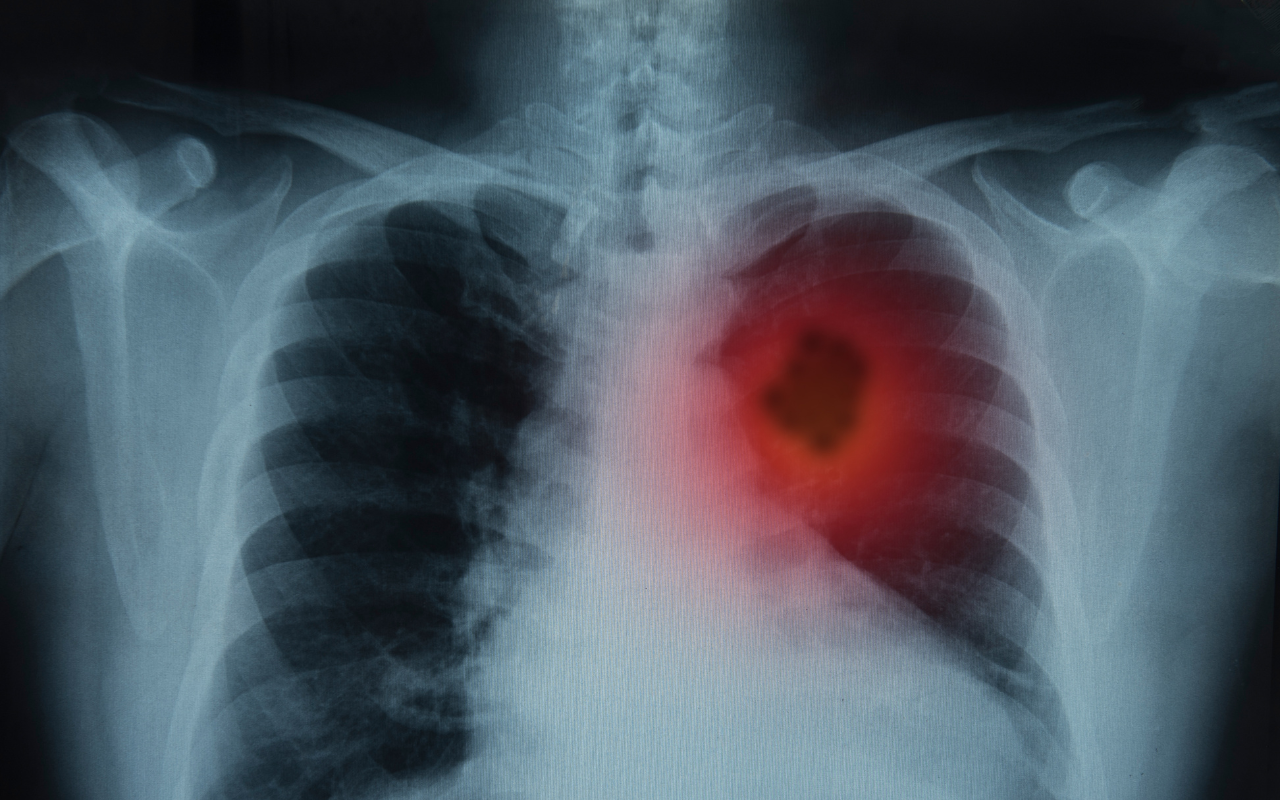

It aims to reduce the number of people dying from lung cancer by offering regular low-dose CT scans to people who smoke, and those who have quit. The aim is to detect and treat cancer early before it has spread.

Lung cancer is the most common cancer and the leading cause of cancer death for Aboriginal and Torres Strait Islander peoples.

Aboriginal and Torres Strait Islander peoples are 2.1 times more likely to be diagnosed with lung cancer, and 1.8 times likely to die from it, compared with non-Indigenous Australians.

Aboriginal and Torres Strait Islander peoples are also more likely to be diagnosed with lung cancer at a younger age than non-Indigenous Australians.